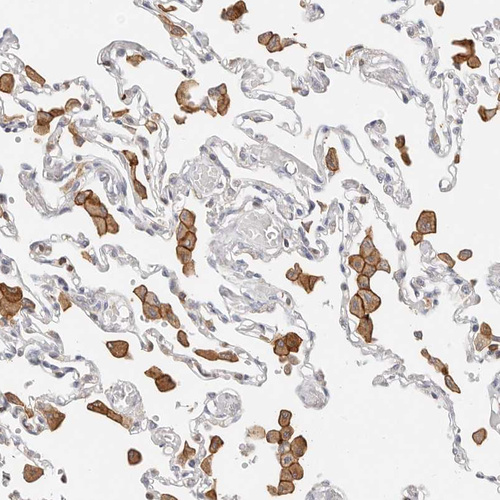

Immunohistochemical staining of human lung shows strong membranous positivity in macrophages.